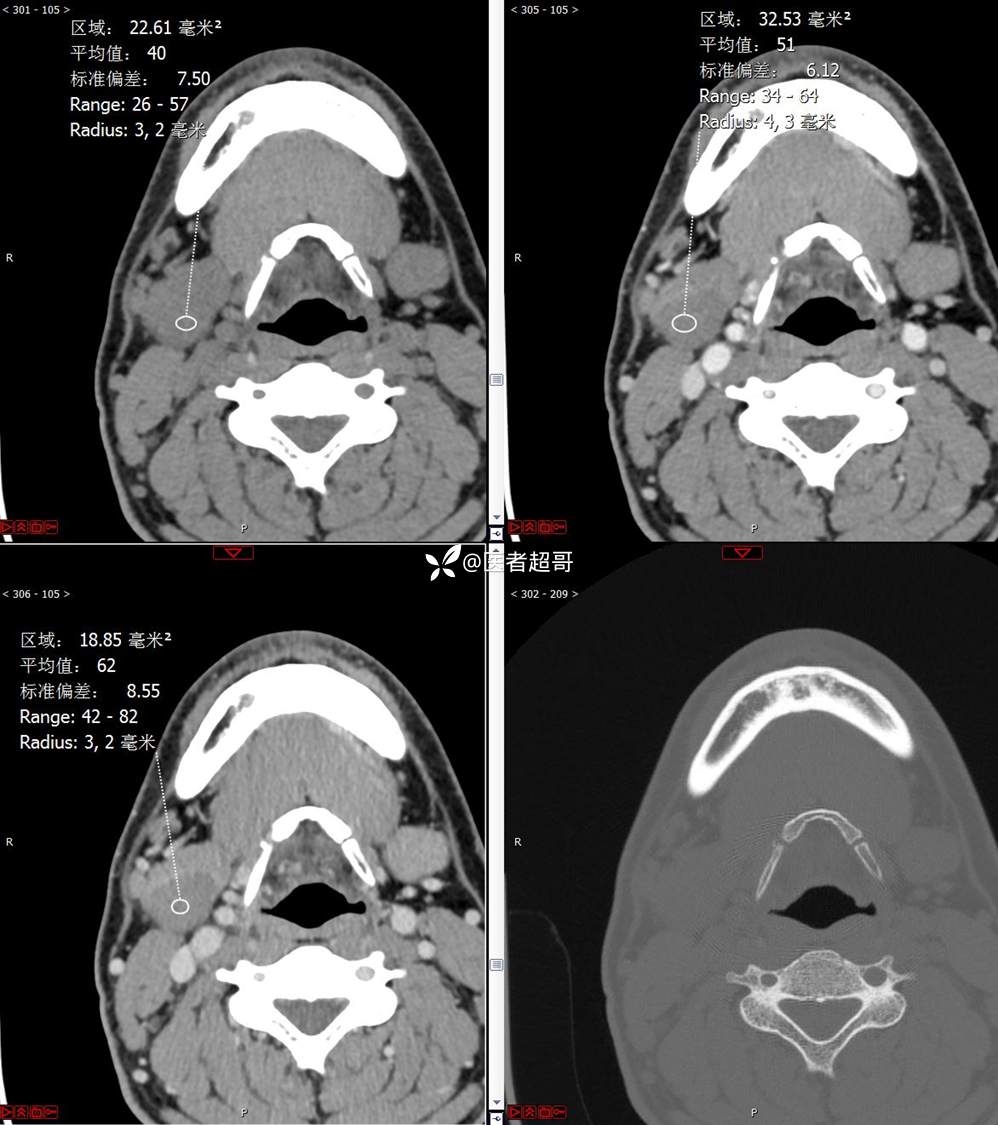

颌下腺结节:青年男性,颌下区无痛性肿物,请分析~~~

主 诉:发现右颌下区无痛性肿物1年。

现病史:患者于1年前发现右颌下区一肿物,肿物约“葡萄粒”大小,无疼痛不适,无进食时颌下区肿胀及疼痛不适。2023-10-1就诊于市中医院行超声检查;未予治疗。肿物体积无明显变化,求进一步治疗就诊于我院门诊,门诊以“颌下肿物”收入我科。患者自发病以来,神志清,精神佳,食欲好,睡眠好,大小便正常,近期体重无明显变化。